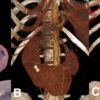

V. Chẩn đoán UIV / CT

– Hai thận xoay trục, cực dưới hướng vào trong phía cột sống.

– Đài bể thận bình thường hướng lên trên ra ngoài => hướng xuống dưới.

– Phần nối hai cực dưới là nhu mô hoặc dải xơ vắt ngang phía trước cột sống.

=> Case lâm sàng 5:

=> Case lâm sàng 6: